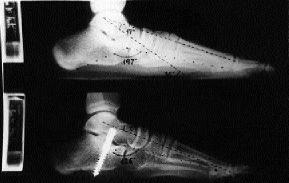

Este procedimiento se basa en la comprensión de la biomecánica del retropié, en la que se interrelacionan como diversos componentes de un mismo movimiento, tanto la flexión plantar, la adducción y la listesis anterior del astrágalo, así como la eversión del calcáneo.19 Todos ellos concurren a nivel de la articulación subastragalina de tal modo que si se frena uno se frenan todos (stop one, stop all).17 En la técnica de calcáneo-stop el tornillo colocado en el margen externo del seno del tarso, apoyándose contra la cara lateral del cuello del astrágalo justo anterior a la apófisis astragalina externa, se opone a la caída plantar, listesis con rotación interna del astrágalo e inclinación valguizante del calcáneo (Fig. 1). La corrección del antepié y arco interno serían secundarias al restablecimiento de la relación astrágalo-calcáneo. Esta corrección mantenida se estabiliza y mejora por la remodelación residual y el retensado espontáneo de las estructuras capsuloligamentosas.1

A

B

C

Figura 1. A: Esquema mostrando las acciones: antilistesis anterior-caída plantar del astrágalo (1), oposición a la inclinación valguizante del calcáneo (2) y a la rotación interna-caída plantar del astrágalo sobre el eje imaginario (3). Radiografías pre y postoperatorias de un niño de 13 años. En proyección AP (B) los ángulos astrágalo-calcáneo y astrágalo-escafoideo pasaron de 19 a 16° y de 59 a 66°, respectivamente. En proyección lateral (C) los ángulos astrágalo-metatarsiano, Costa-Bartani y flexión plantar del astrágalo pasaron de 17 a 0°, de 147 a 136° y de 36 a 22°, respectivamente.